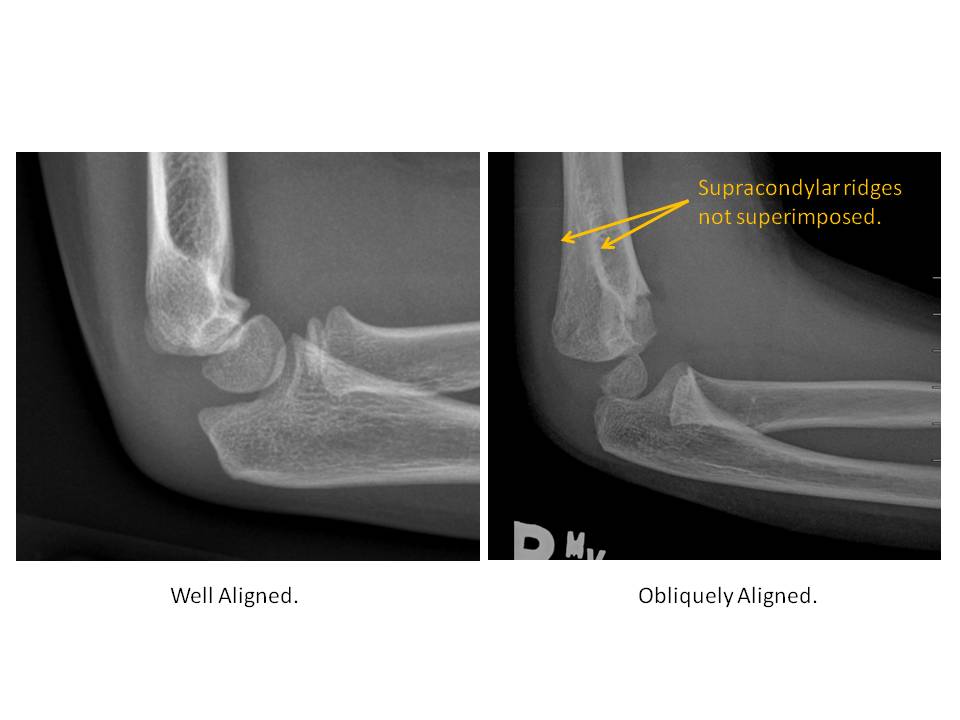

| Alignment | Correct Answer | Your Answer |

|

No | NA |